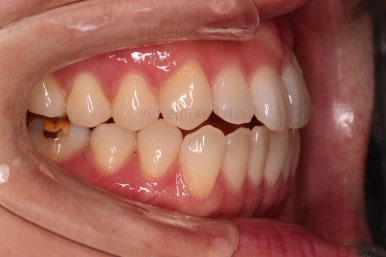

삐뚤한 덧니를 가지런하게 하기 위해서 필요한 부분의 어금니를 순차적으로 뒤로 밀어줍니다.

자세히 보면 치아 사이사이에 틈새가 생기는게 보이죠?

틈새를 일부러 만들어 해당 공간으로 덧니를 가지런하게 하는 원리입니다.

두번째 세트를 진행 중입니다.

부족한 부분을 좀 더 맞춰주고요.

마무리를 하게 됩니다.